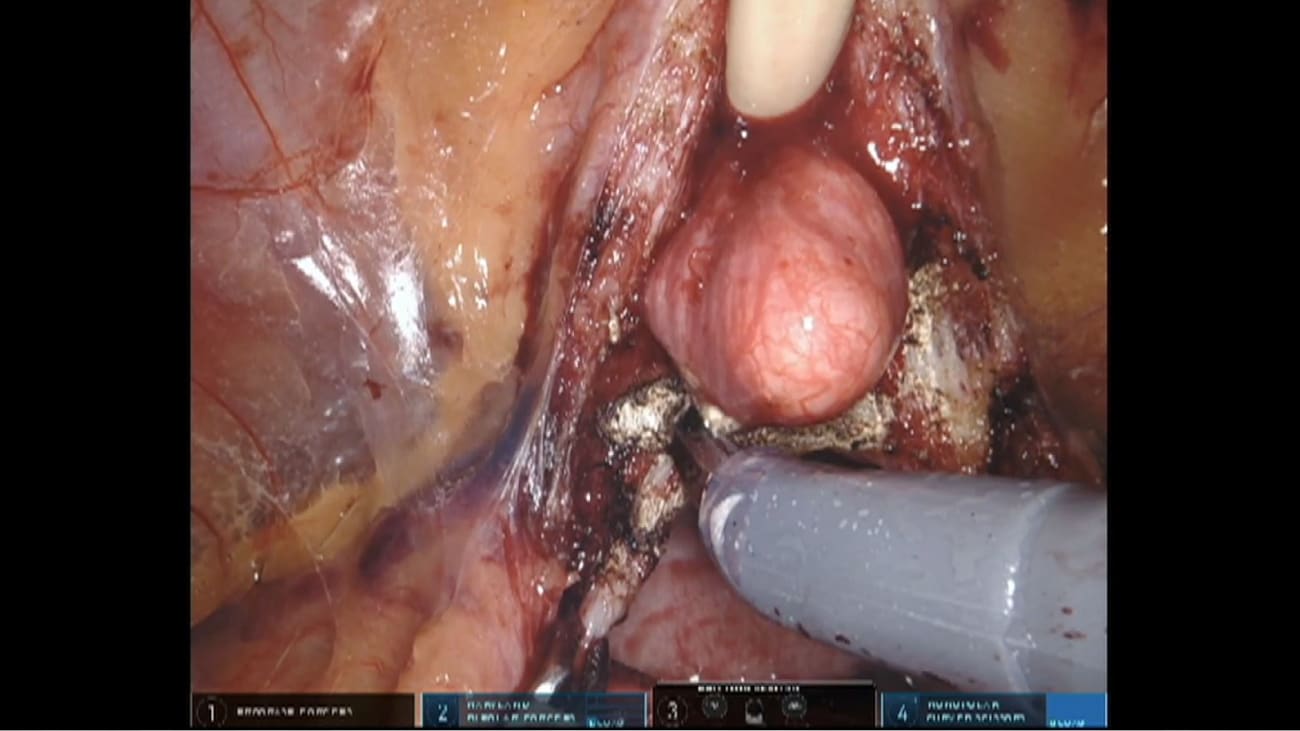

Good morning ladies and gentlemen. This film demonstrates a robotic assisted radical prostatectomy. With the tunnel and hood technique by dr ashe to armor. The patient is a 74 year old man who presented with minimal, you know, prior surgery and a prostate biopsy showing gleason three plus four prostate cancer. Four calls on the right with up to 40% involvement. His MRI showed a 26cc prostate with a 1.4 centimeter Pirates four lesion in the right, mid peripheral zone and no extra counselor extension. This is a schematic of the M. R. I. Findings with the lesion shown in red Based on this using the in House Nama Graham predicting extra capsule extension. The risk of ec and SV. I on the right is 12 and 4% respectively and negligible on the left. With a proposed grade of nerve sparing of two on the right and one on the left. The tunnel and hood technique is a paris arosa will supervise cycle recess sparing approach that provides an endo pelvic fashionable window for entry into the neurovascular triangle and so allows early neurovascular bundle release. It is versatile in that it allows preservation of the bladder neck with dissection of any medium loans but at the same time taking care of the Euro Terrien or offices. It doesn't disturb the anatomy of the pouch of Douglas and preserves important structures contributing to the anterior hood, which we will discuss during the film. Later, the film starts after the truckers have been placed. Doctor to our begins his dissection, dividing the Eureka's to drop the bladder. But with the tunnel techniques staying in the midline in order to spare the lateral tissues. During this part of the procedure he uses fine sharp dissection and electro coagulation for homeostasis. The endo pelvic fascia is generally only incised when there is a large prostate or an aggressive cancer for the larger prostates, it gives more mobility and for the aggressive cancers, more vision during the lateral dissection. In keeping with the tunnel technique for this patient, the lateral tissues are spared and the end of pelvic fascia is preserved on both sides. For the bladder net transaction an incision is made in the anterior bladder wall, right above the prostate. Over cycle junction. The Foley Catheter is then lifted and held eventually using the 4th arm. In this case you can see a large median lobe and the dissection continues beneath it onto the posterior bladder wall. In a posterior recess bearing approach, the presence of a median lobe may be missed. An incision is made through the post area, bladder neck which takes you onto the retro trigo nor fibromyalgia secular layer overlying the seminal vesicles having dissected through the retro trig onal fibra muscular layer, the visa deferential and seminal vesicles are clearly visible. Following this both ways are dissected, lifted up and divided separately. In this case dr tiwari has chosen to dissect and divide the right vous and then dissect the entire right seminal vesicles before moving on to the left side. When dissecting the seminal vesicles, it is helpful to find the median a vascular plane between the body of the several vehicles and the surrounding fashion, which is nicely demonstrated here. This plane could also be traced approximately to identify arteries entering the seminal vesicles from below and laterally. Once the vase are sectioned, it is important to try and minimize dia thermic using clips for vascular control whenever possible to prevent pelvic plexus damage, especially lateral to the seminal vesicles and near the tips where the cell bodies of the pelvic plexus can be found as the dissection of the seminal vesicles continues. It's helpful to understand the neuro anatomy of the pelvic plexus. The pelvic plexus consists of the proximal neurovascular plate related to the tips of the seminal vesicles. The neurovascular bundle itself located in a poster or lateral groove on the side of the prostate and the accessory nerve pathways on the lateral surface of the prostate. After seminal vesicles dissection, the prostate is lifted with the fourth arm setting up the posterior dissection which starts with the incision of dental villiers fascia in the midline. The posterior dissection is completed at the prostatic apex on the pelvic floor and then extends laterally where three different tissue layers are encountered, allowing for different grades of nerve sparing For grade one nerves bearing dissection has continued in a plain beneath the inconsistent loose layer of vascular Fashir onto the prostatic pseudo capsule itself, maximizing sparing of the accessory nerve pathways for gray to nerve sparing dissection is through the venus layer of fascia beneath the formal lateral prostatic fascia, which will conserve the majority of accessory nerve pathways. The grade three nerve sparing dissection is outside the lateral prostatic fashion, sparing the vato Fashir and conserving the predominant neurovascular bundle but not the accessory nerve pathways. Grade four nerve sparing or non nerve sparing is when the lateral prostatic fascia is excised and left on the prostate specimens. As discussed. When we show the schematic at the beginning of the film, this patient is having grade one nerve sparing on the left and grade two on the right. With the posterior dissection complete. The pericles will be clipped and divided before the dissection continues on towards the prostatic apex on the left. This will be directly on the pseudo capsule. In keeping with grade one nerve sparing and on the right, within the venus layer of fashion beneath the lateral prostatic fascia consistent with Grade two nerve sparing any perforating arteries entering the prostatic catchall that are encountered are cut sharply within the appropriate plane. Sometimes for the retro ethical dissection, the prostate is lifted. Anti really towards the pubic synthesis and the camera lens has changed to 30° optic with upward direction. Using blunt dissection with monopoly scissors and retracting the apex away from the urethra it's possible to gain 1 to 2 millimeters of member anus urethra length. Prior to transaction The camera lenses then changed back to 0° optic for the anterior dissection here you can see he is dissecting directly onto the prostatic pseudo capsule. As he moves towards the apex. With the nerve sparing complete, he dissected the detroiter apron off the anterior surface of the prostate from left and right sides and then from the midline. The dead trees. A Apron has three layers anterior, middle and posterior. The anterior layer passes posterior lee to the devastated pubic cockatiel fibers. Diffuses Antero inferior early and anchors onto the posterior surface of the pubic bone. The middle air is loose and joins the fashions sheath of the dorsal vein complex. Lastly, the posterior layer encloses and extends onto the prostate to form the anterior fiber muscular strom A. Of the prostate. The Detroit to open is a key part of the anterior fiber muscular Strama, a thick sheet of tissue over the entire anterior external surface of the prostate, devoid of any glandular tissue. It can safely be dissected off the surface of the prostate and preserved to maintain the continent's mechanism and limit dissection near the urethral sphincter. He then moves on to the a pickle dissection, another crucial part of radical prostatectomy with implications for both oncological and functional outcomes here. Part of the a pickle dissection is done and the urethra is seen emerging from the prostatic apex. The dorsal vein is then litigated before the a pickle dissection is completed. Positive surgical margins are more frequently reported at the prostatic apex and have been associated with a higher risk of recurrence but preservation of maximum urethral length is associated with improved postoperative continents. Here you can see the eureka has transacted a few millimeters from the prostatic apex to reduce the risk of positive surgical margins but also to maximize urethral stump length. In this case an extra piece of tissue is taken from the post area urethra margin for frozen section in summary preservation of the endo pelvic fascia that Patricia, apron nerve sparing and maintaining urethral stump length. All help to keep the urethral sphincter incontinence mechanism intact as much as possible to maximize earlier return of continence here you can see the post area urethral sections being placed before the visoko urethral anastomosis which he comes back to after doing the post area reconstruction. Once the urethra is transected, the specimen is bagged and then removed for neurosurgery procedure. The posterior bladder neck and donald villiers muscular fashion plate reconstruction represents the first step of the total anatomical reconstruction By reconstructing the post area plate. 1st we secure enough support to the posterior urethra, which also includes the retro trig onal layer of tissue and the Veysel stumped for extra support. The main purpose of this surgical step is to minimize urethra sphincter eric sliding to provide support to the vsco urethral anastomosis to bring the bladder neck close to the urethral stump and also to provide an adequate fulcrum of contraction for the rhabdo sphincter once the posterior muscular fashion plate has been reconstructed with denim villiers fashion reconstruction of the posterior bladder wall has begun with Velox futures. This is done in two layers. Once the second layer of the Postwar reconstruction is complete, the Vlach and vicryl sutures are tied approximately close to the opening of the bladder. With the posterior reconstruction finished, he retrieves the urethral suits as he placed earlier on and completes the visit co urethral anastomosis over the catheter.